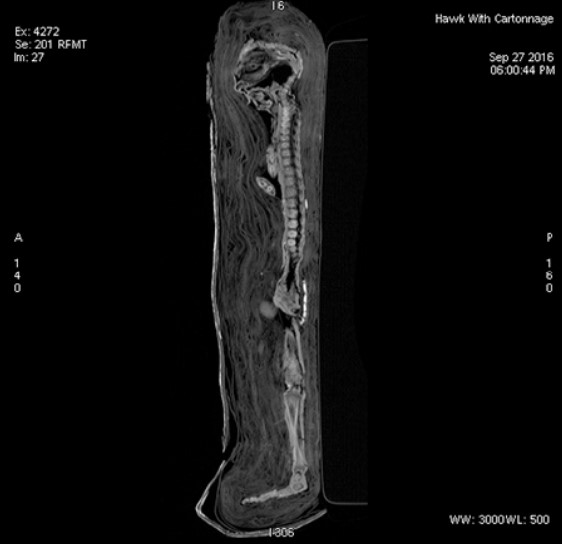

In 2016, as part of Maidstone Museum’s Ancient Lives project, their mummified collections, comprised mostly of animals, were CT scanned. Shockingly, EA 493 Mummified Hawk (Ptolemaic Period, 300bce) didn’t contain a hawk, it contained a human.

Inside of a small cartonnage, painted with a gilt hawk face and wings, but human feet in sandals, and references to Horus, the falcon-headed god of the sky (show more on screen), they discovered a human male fetus mummified with his arms across his chest.

“The mummy is housed in a plaster case embellished with the face of a hawk and hieroglyphics discussing Horus, an ancient Egyptian god of kingship and the sky bearing the head of a falcon. Careful inspection reveals, however, markings that look like human sandals at the bottom end of the case.”

Andrew Nelson and Sahar Saleem among others did further testing: the fetus miscarried at around five months gestation due to severe anencephaly, in which the brain and skull did not develop. His head would not have looked human and his family may have associated him with Horus because of it.